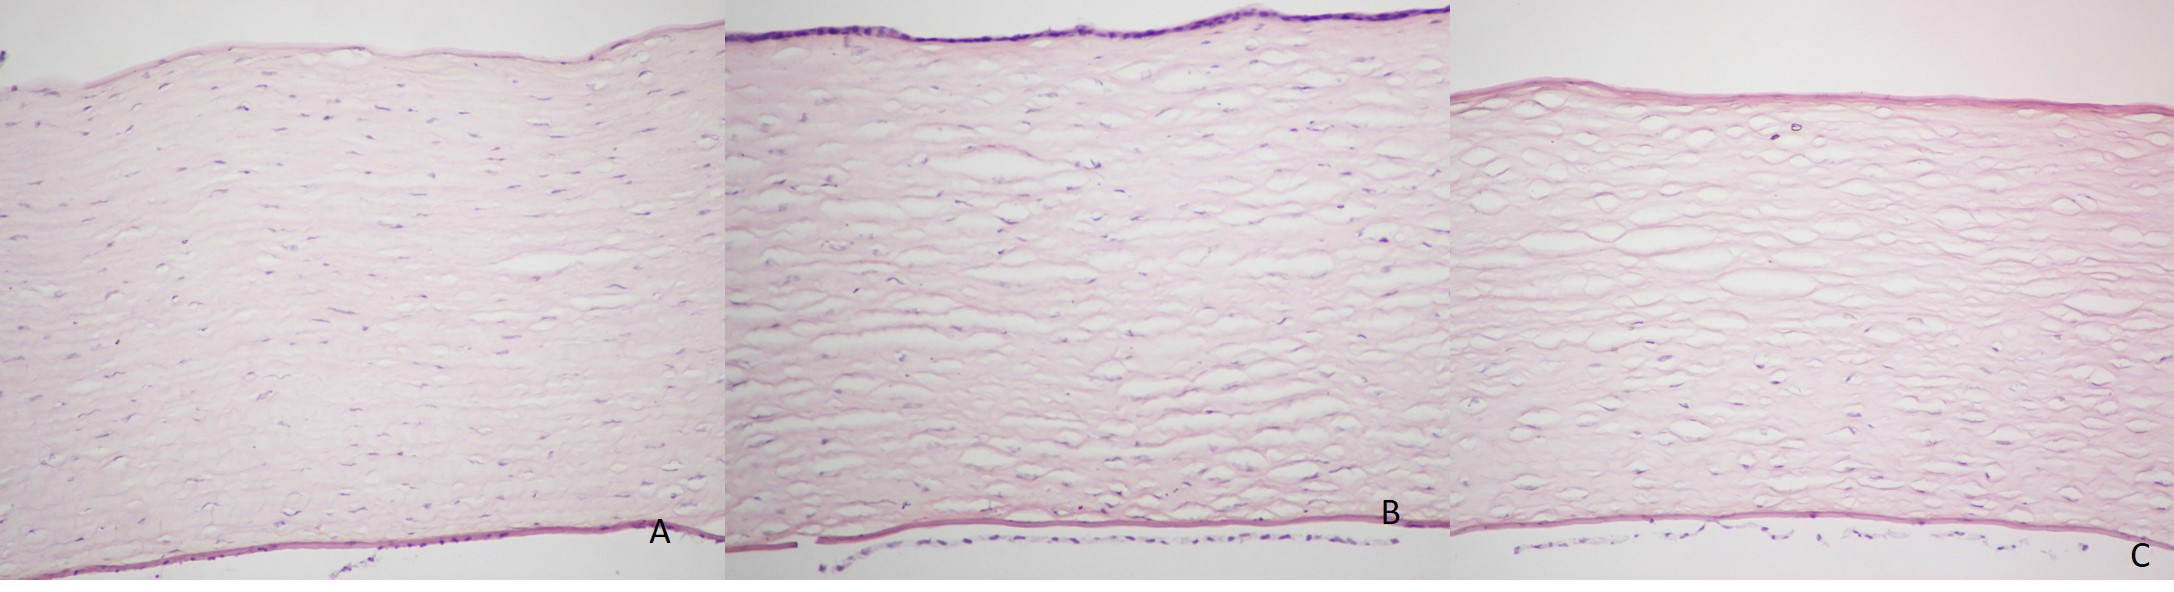

Figure 7.

Representative images of the HE stain. In the PBS group (

A

) and the GP-CXL group (

B

), the corneal structures are normal (200X).

C

: In the UVA-CXL group, keratocytes are absent in the anterior and middle stroma.